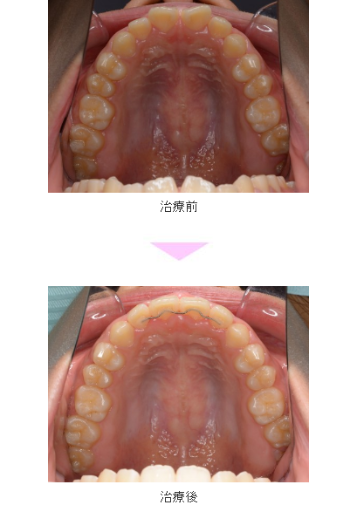

全顎矯正と部分矯正へのアプローチ : 非抜歯治療と抜歯治療の。所沢の矯正専門医院 VAN矯正歯科|所沢駅徒歩1分。Vol.186 上顎前突に対する段階的アプローチ:非抜歯から抜歯治療へ。「全顎矯正と部分矯正へのアプローチ : 非抜歯治療と抜歯治療の選択基準」山地正樹 / 山地晃二郎定価: ¥ 180001度も読んでいない新品ですが素人の自宅保管になります。他にも多数出品しておりますので是非宜しくお願い致します。歯を抜かない矯正治療(非抜歯矯正)|東京都港区麻布十番のUC矯正歯科。中身は読んでいないので新品同様綺麗ですが、表紙やカバーには新品ですが保管による小傷や汚れがある場合がありますので完璧な新品を求めている方は落札をご遠慮下さい。ボツリヌス療法のすべて : アジア人への応用。【裁断済】臨床区域麻酔科学書。#山地正樹 #山地晃二郎 #本 #自然/医療・薬学・健康